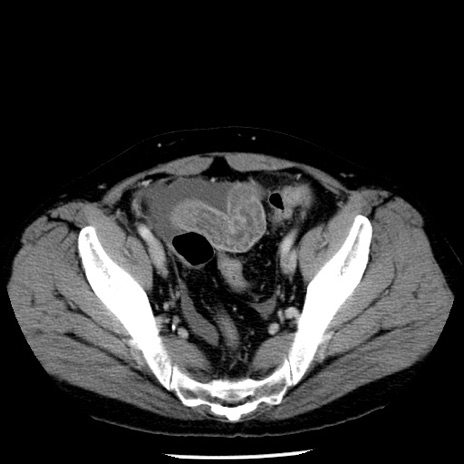

症例29(横断像)

【症例】40歳代男性

【現病歴】2日前から胃痛あり。徐々に周期的な激痛に変化した。本日になっても激痛があるため受診。

【身体所見】意識清明、BT 38-39℃台あり、腹部:膨満、やや硬、右下腹部に圧痛あり。

【データ】WBC 8500、CRP 23.26